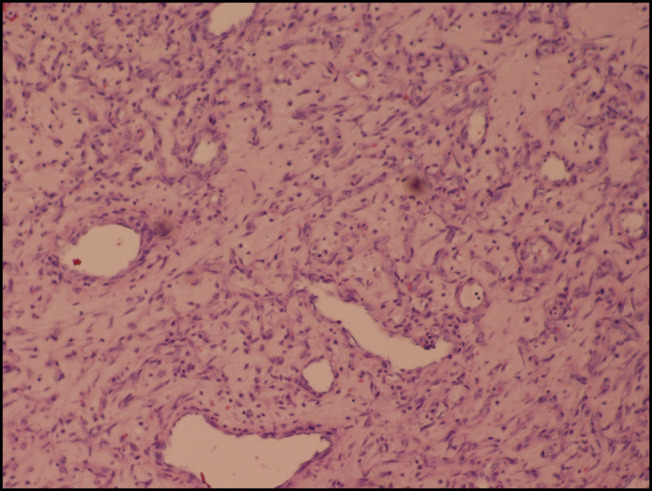

化脓性肉芽肿是一种良性血管病变,常见于皮肤和粘膜,但很少发生在胃肠道。本病例突出显示小肠内的大PG,引起慢性贫血,并作为肠套叠的先导点。我们讨论其诊断挑战,潜在的误诊,和治疗方案。本病例强调了临床医生对pg非典型表现的认识的必要性。它还强调了彻底评估不明原因贫血和间歇性梗阻患者的重要性,确保及时诊断和适当管理这种罕见的胃肠道疾病。

Pyogenic granulomas (PGs) are benign vascular lesions usually found in the skin and mucous membranes but rarely in the gastrointestinal tract. This case highlights a large PG in the small intestine, causing chronic anemia and serving as a lead point for intussusception. We discuss its diagnostic challenges, potential for misdiagnosis, and treatment options. This case underscores the need for awareness among clinicians regarding atypical presentations of PGs. It also highlights the importance of thorough evaluation in patients with unexplained anemia and intermittent obstruction, ensuring timely diagnosis and appropriate management of this rare gastrointestinal condition.